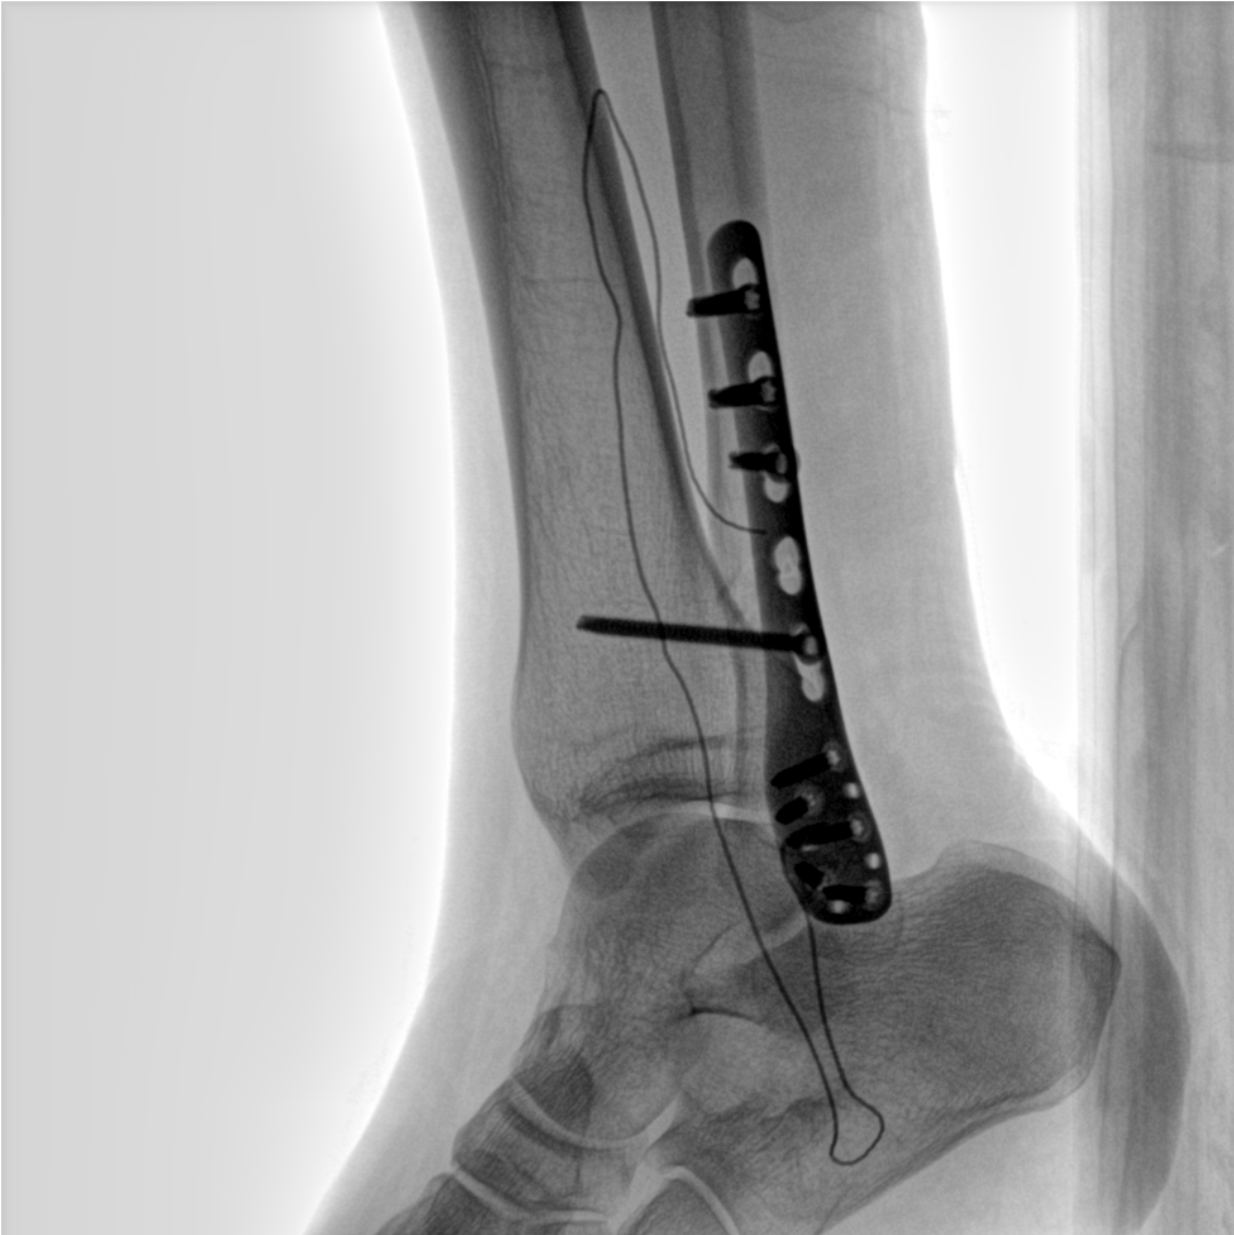

術中三維成像和橫斷面圖像提供多角度的手術診斷信息,輔助醫生進行術中評估判斷,諸如骨折復位情況和內植入螺釘的尺寸和位置,輔助手術更好地完成。

提供更大的術中三維成像視野,采集更多圖像信息,可一次拍全全段頸椎、全段腰椎、七節胸椎、雙側骶髂關節、股骨頭及單側盆骨。